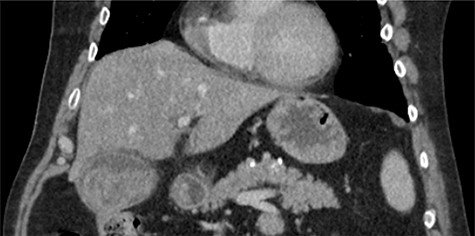

The emergency physicians arranged an urgent non-contrast computerized tomography (CT) scan of the abdomen and pelvis. This revealed hyperdense nodular soft tissue filling the gallbladder lumen with a non-thickened but prominent gallbladder wall, as shown in Fig. 1. There was biliary dilatation, with extensive fat stranding and fluid surrounding the gallbladder neck, porta hepatic region and common bile duct. The reporting radiologist’s differentials included malignancy or haemorrhagic cholecystitis, and magnetic resonance imaging (MRI) was advised.

Coronal non-contrast CT of abdomen on day of presentation, showing hyperdense nodular soft tissue filling the gallbladder lumen.